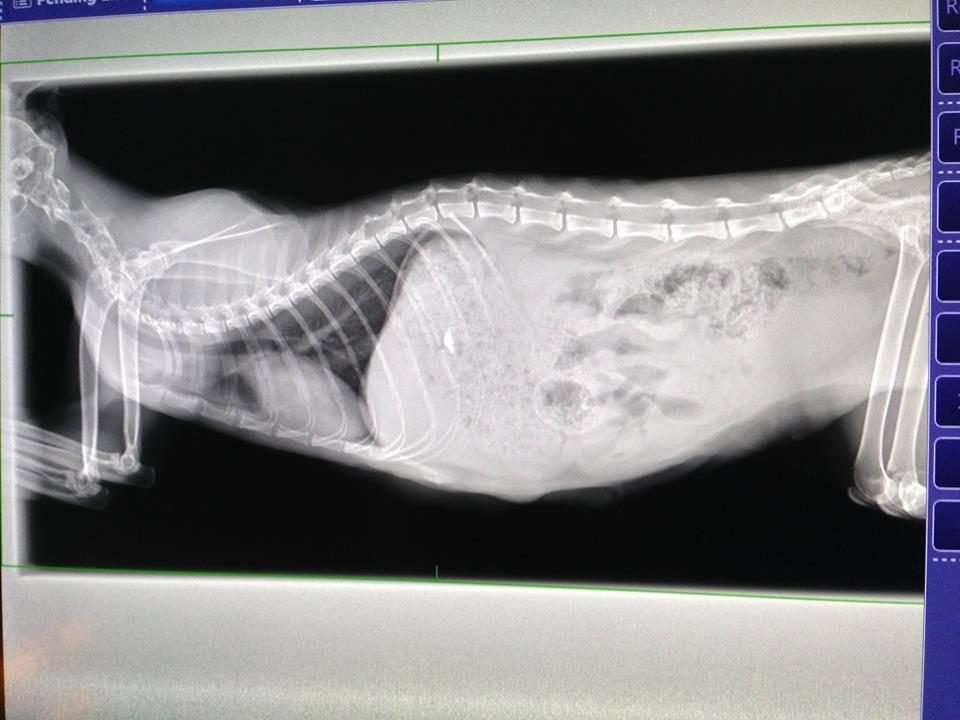

X光中可看到腸子中有成型的顆粒糞便且塞滿了食物

且心臟略大,不過許多生產完的媽媽會有心臟略大的現象項

之後會再慢慢縮小為正常大小

另還做了腸道的超音波,發現腸性膜淋巴結腫大

(長期拉肚子造成發炎也會使淋巴結腫大)

還有在膀胱處有看到疑似菌塊,其餘目前看來並無特別異狀